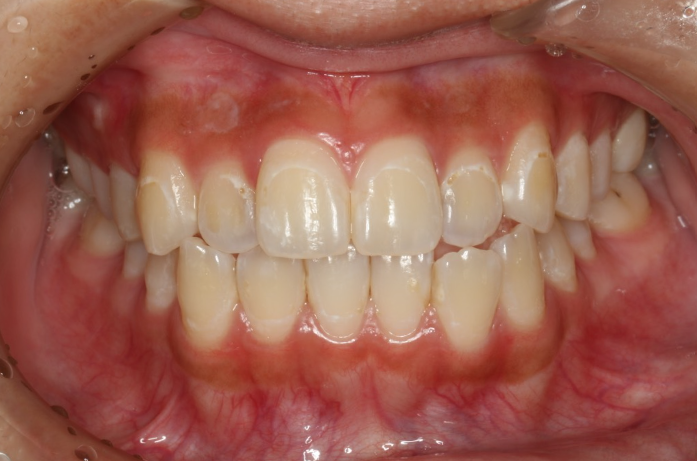

| 患者様データ | 60代 男性 |

| 来院時の主訴 | 「歯石が溜まりやすい。歯磨きすると出血するのも治したい。」 |

| 医院の診断 | 歯周病 |

| 通院期間 |

3か月 |

| 来院回数 | 6回 |

| 治療費 | 総額:保険適用診療 【内訳】 歯周病検査・歯磨きや生活習慣指導・歯石取りクリーニング |

| リスクと副作用 | メインテナンスが必要、正しい歯磨き習慣が必要不可欠 |

| ここがこだわりのポイント!☝ | 歯周病の原因は様々ですが、メインの原因は細菌感染です。こちらは中等度の歯周病で来院された患者様です。日々の歯磨き習慣を見直していただき、正しいブラッシング法を身につけたことで健康な歯肉を取り戻しました!こちらの治療結果も患者様の努力の賜物です! |